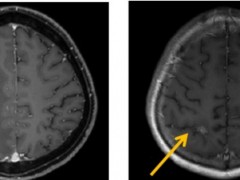

TCR-T细胞疗法NY-ESO-1治疗多线耐药的晚期肺癌,患者部分缓解,肿瘤大幅缩小

肺癌2025-12-11